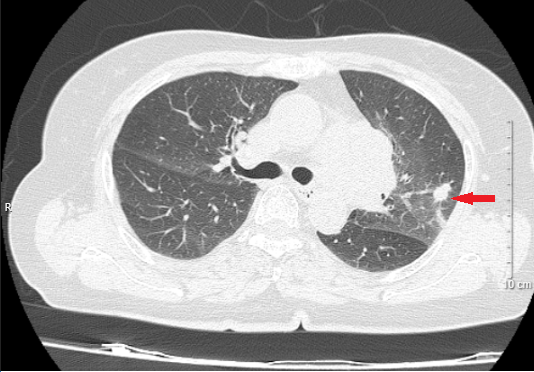

• Chụp cắt lớp vi tính lồng ngực: Trung thất giữa cạnh trái khí quản, rốn phổi trái có khối u với  kích thước 35 x 36 mm, bờ thùy múi, ngấm thuốc không đồng nhất, ôm quanh mạch máu lân cận. Nốt đặc thùy trên phổi trái có đường kính khoảng 10 mm, bờ đều, ranh giới rõ. Không có hạch trung thất.

Hình 1: Hình ảnh cắt lớp vi tính lồng ngực lúc mới chẩn đoán (mũi tên xanh: khối ở trung thất giữa; mũi tên đỏ: nốt đặc ở phổi cùng bên).